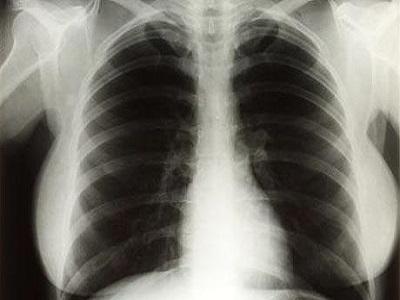

Hình ảnh minh họa phổi bình thường và phổi bị COPD